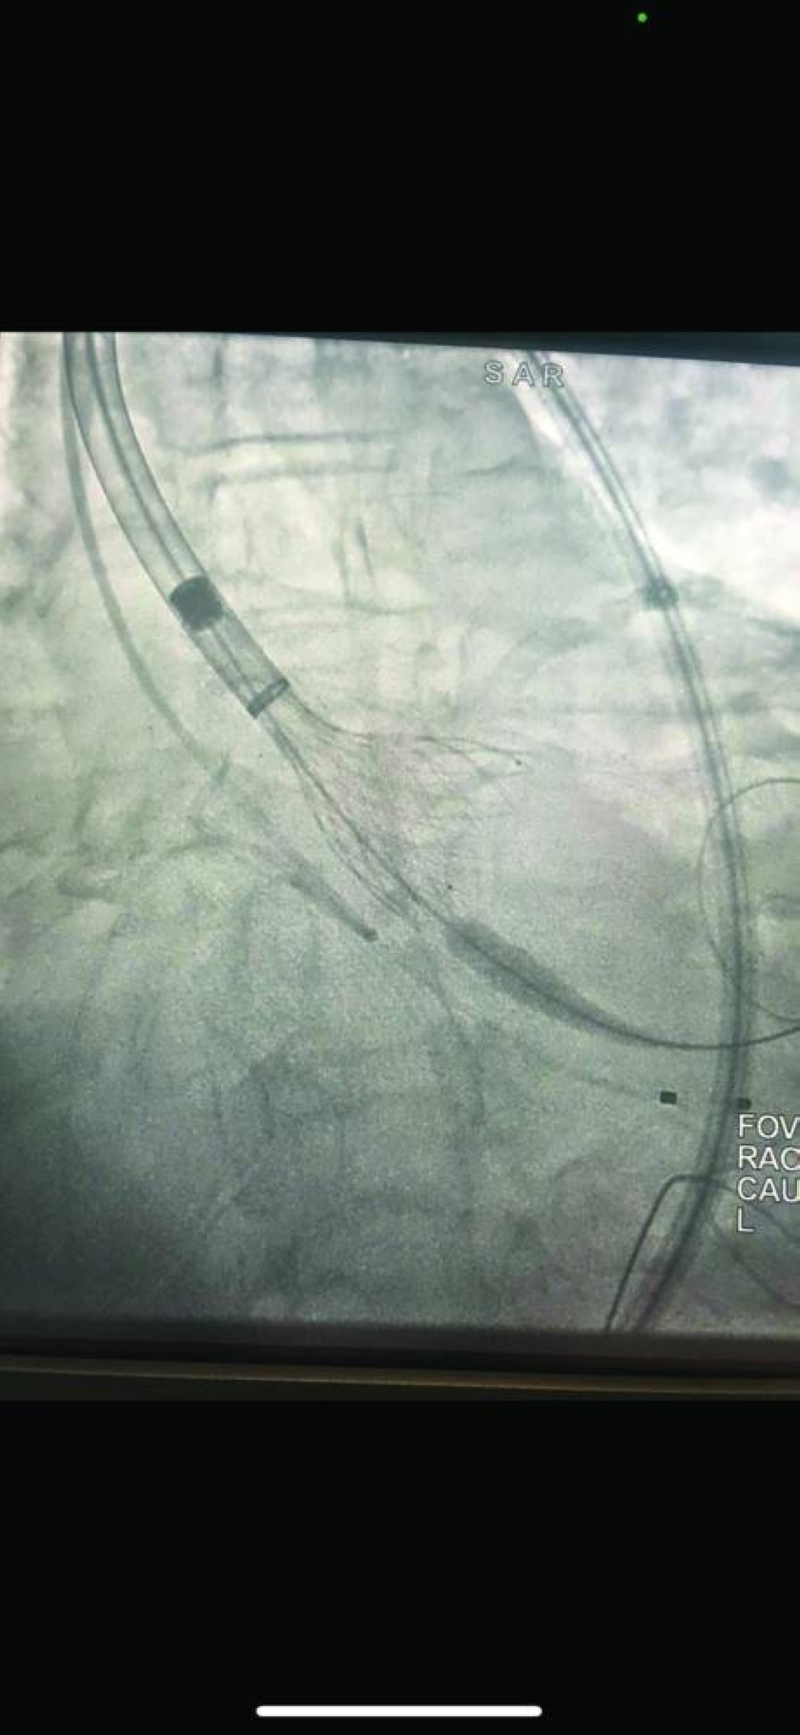

فقد نجح فريق مركز صباح الأحمد للقلب، المكون من استشاريَي القلب والقسطرة في المركز الدكتور نادر عيسى العسعوسي، والدكتور أحمد سعيد طه، في تبديل الصمام الأورطي للمريض بالقسطرة (TAVI) وتركيب دعامات بالشريان التاجي الأيسر والأيمن، فيما تمكن فريق مستشفى مبارك الكبير المكون من استشاري جراحة الأوعية الدموية الدكتور عبدالله الفواز، واستشاري الأشعة التداخلية الدكتور حسين جراغ، من إصلاح تمدد شرياني كبير بالأبهر البطني، كان على وشك الانفجار (EVAR for AAA)، وذلك في آنٍ واحد وبصفة عاجلة، وبدون جراحة لإنقاذ حياة مريض، يقارب عمره من نحو 100 عام، حيث كان المريض قد أُدخِل إلى العناية المركزة القلبية بمركز صباح الأحمد للقلب، في حالة حرجة، وهو يعاني من جلطة بالقلب وارتشاح رئوي حاد، وتجمُّع كبير للسوائل بالصدر (massive bilateral pleural effusion)، مما أدى إلى فشل تنفسي حاد. غير أن حالة المريض بعد هذا الإنجاز الطبي استقرت، وتماثل للشفاء بعد وضعه تحت العناية المكثفة، إلى أن خرج للمنزل في حالة مستقرة.

وقد تدهورت حالة المريضة على مدار سنتين، وأدخلت من الطوارئ إلى العناية المركزة للقلب بالمركز وهي تعاني من صدمة قلبية واحتشاء بعضلة القلب (acute MI and cardiogenic shock) وتجمُّع شديد للسوائل بالجسم (generalized anasarca )، حيث تم إجراء قسطرة تداخلية عاجلة، وتركيب 4 دعامات بالشريان التاجي الأيسر الرئيسي والتاجي الأيمن، تحت الدعم من المضخة القلبية الرئوية (ECMO)، وبعد ذلك تبديل الصمام الأورطي بالقسطرة (TAVI) من قبل فريق تبديل الصمام الأورطي بالقسطرة.

• تركيب 4 دعامات بالشريانين التاجي الأيسر الرئيسي والتاجي الأيمن، تحت الدعم من المضخة القلبية الرئوية (ECMO)